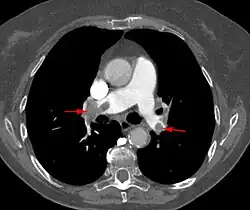

- Lungenembolie (= venöse Embolie): Der Embolus stammt aus Körpervenen und verstopft nach Passage der rechten Herzhälfte Lungenarterien.